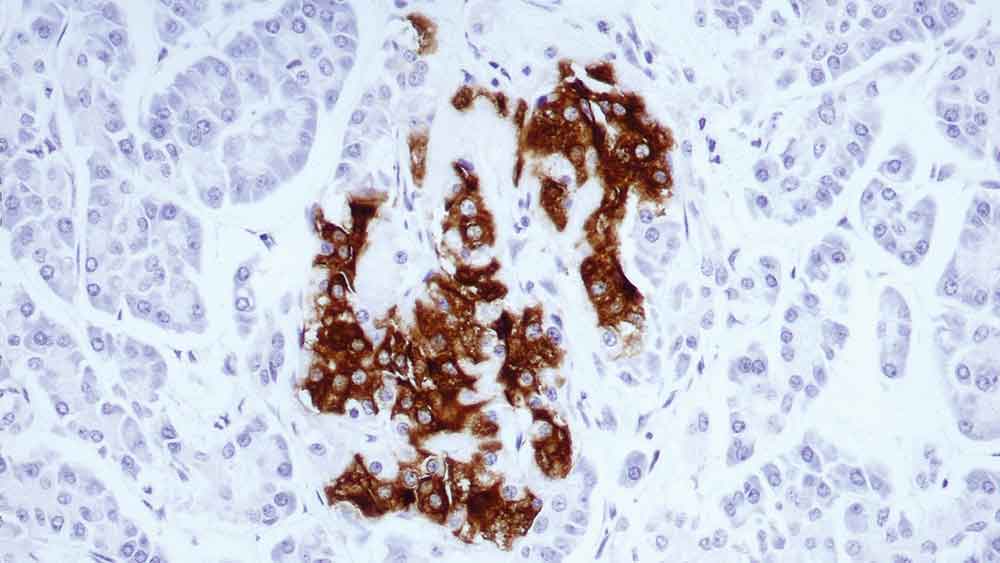

Human tonsil: immunohistochemical staining for CD19. Note membrane staining of B cells. CD19: clone BT51E

O CD19 faz parte da superfamília de imunoglobulinas e possui dois domínios como o de Ig. É uma glicoproteína de cadeia simples presente na superfície de linfócitos B e células dendríticas foliculares do sistema hematopoiético.

O CD19 é um regulador crucial no desenvolvimento, ativação e diferenciação de células B. Em células B, o CD19 se associa com o CD21, CD81 e CD225 (Leu-13), formando um complexo de transdução de sinal.

A expressão do CD19 acontece a partir do primeiro estágio da linhagem de células B que se pode ser reconhecido até o desenvolvimento de uma diferenciação de células B, mas se perde na maturação para células de plasma.